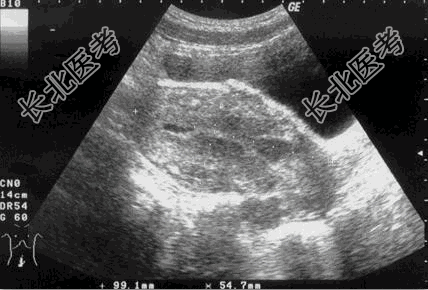

- [材料题] 患者女性,54岁。 阴道不规则出血40余天。超声检查如图。

- 简答题1、该患者最可能的诊断是?

- 简答题2、最具有确诊意义的检查是?